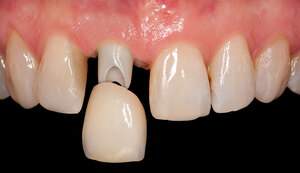

インプラントとは、虫歯や歯周病などの様々な原因により歯が失われてしまったところへ、人工の歯の根=人工歯根(インプラント)をつくり、その上に被せ物を装着する治療法のことです。

インプラントの特徴は、歯根まで再現し骨とインプラントが直接結合することにより、天然歯と同じような見た目・機能の両面において元の自然な状態へ近づくことができ、またしっかり噛むことができます。

インプラントの構造は、上部構造・アバットメント部(支台部)・歯根部の3つの構造から成り立っています。

上部構造は、いわゆる被せものを指しており、歯の部分です。

アバットメント(支台部)は、上部構造と歯根部をつなぐ役割を果たしています。

歯根部は、チタン製で、この部分と顎の骨が結合します。